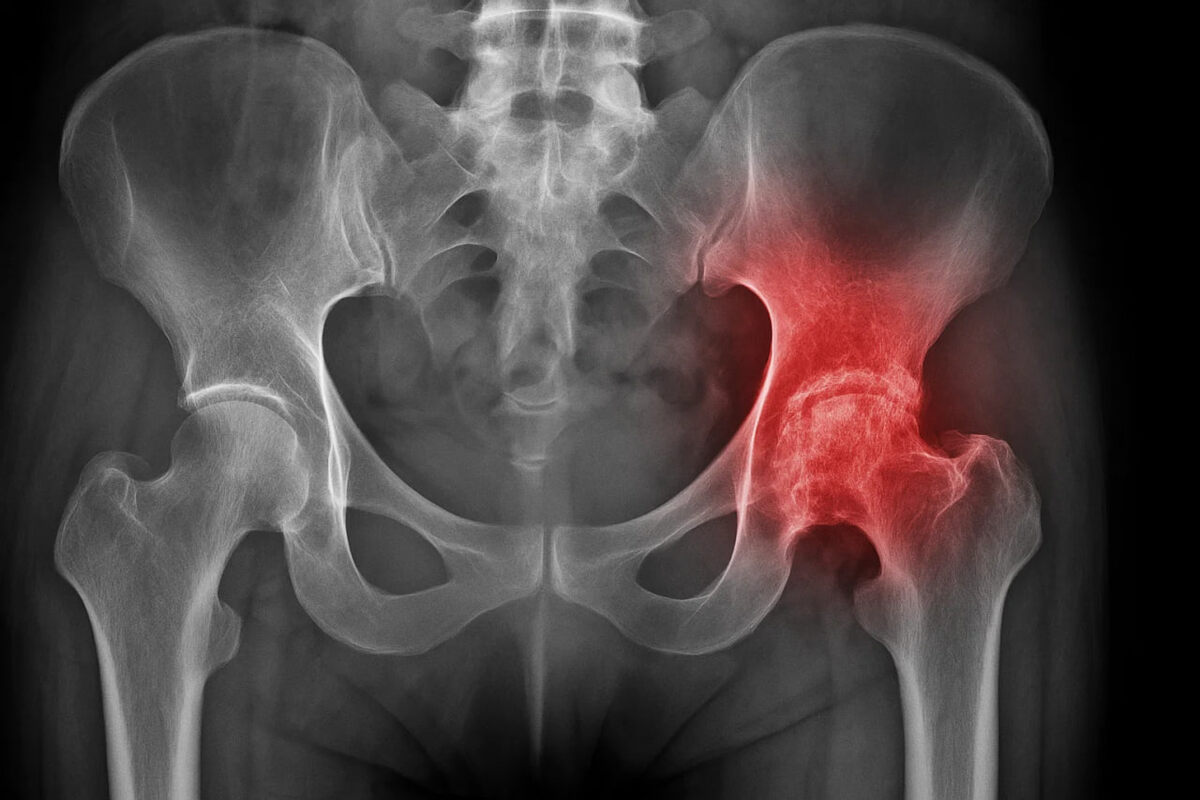

🔥 КОКСАРТРОЗ — ТИХИЙ ВРАГ СУСТАВОВ Это разрушение тазобедренного сустава, которое начинается незаметно: лёгкий дискомфорт при ходьбе, редкие боли после нагрузки. Но постепенно хрящ стирается, сустав теряет подвижность и человек буквально перестаёт ходить. ⚠️ Чем он опасен: ⏺постоянная боль, которая не проходит даже ночью ⏺невозможность подняться по лестнице, пройти даже несколько шагов ⏺деформация сустава, укорочение ноги ⏺полная потеря самостоятельности и зависимость от посторонней помощи ⏺на поздних стадиях — только эндопротезирование Коксартроз не щадит никого: если его не лечить, человек оказывается прикованным к постели или инвалидному креслу.